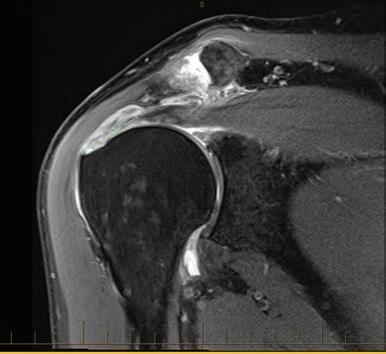

the line? Dr David Colvin 52 Imaging of the knee Dr Gavin Watson 55 Shoulder instability surgery: do it right, do it once Dr William Blakeney 61 A new health paradigm Dr

Rotator cuff repair – where do we draw

This magazine has been printed using solar electricity, and the paper is manufactured with elemental chlorine-free pulps. Both printer and paper manufacturer are certified to ISO 14001, the world’s highest environmental standard. 6 Gestational diabetes is serious Dr Emily Gianatti 39 Rule change around medical abortion Dr Alison Creagh 41 Students want more GP time Sarah Bresnehan 60 Brain aneurysms Dr Ruchi Kabra Environment ISO 14001 57 Resurfacing hip joints A/Prof Piers Yates